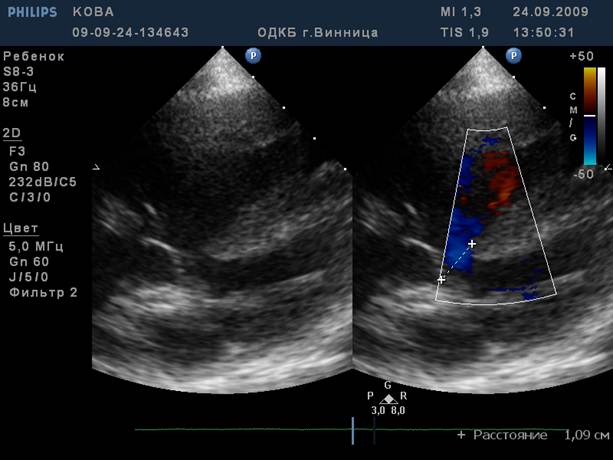

Об‘активно. Стан дитини середньої важкості. t 36,3 Шкіряні покриви бліді, „мармуровий” малюнок шкіри, періоральний та періорбітальний ціаноз. Задишка до 50 за хв.. Аускультативно – жорстке дихання, вологі та сухі хрипи. Пульс 146 за хв., ритмічний. Серцевий поштовх розлитий. Межі серця розширені вліво. Аускультативно – I тон на верхівці звучний,II акцентований та роздвоєний над легеневою артерією, систолодіастолічний шум в лівій підключичній ділянці. Печінка + 2 см. На ЕКГ – гіпертрофія лівого передсердя та шлуночка. На рентгенограмі – кардіомегалія за рахунок гіпертрофії лівого передсердя та шлуночка, підсилення легеневого малюнку, корені легень застійні.

На ЕхоКГ – поток крові з місця біфуркації легеневої артерії в протилежному (до датчика).

1. Поставити клінічний діагноз.

2. Які гемодинамічні зміни обумовлюють клінічну картину захворювання?

3. В чому полягають педіатричні аспекти лікування даного захворювання.